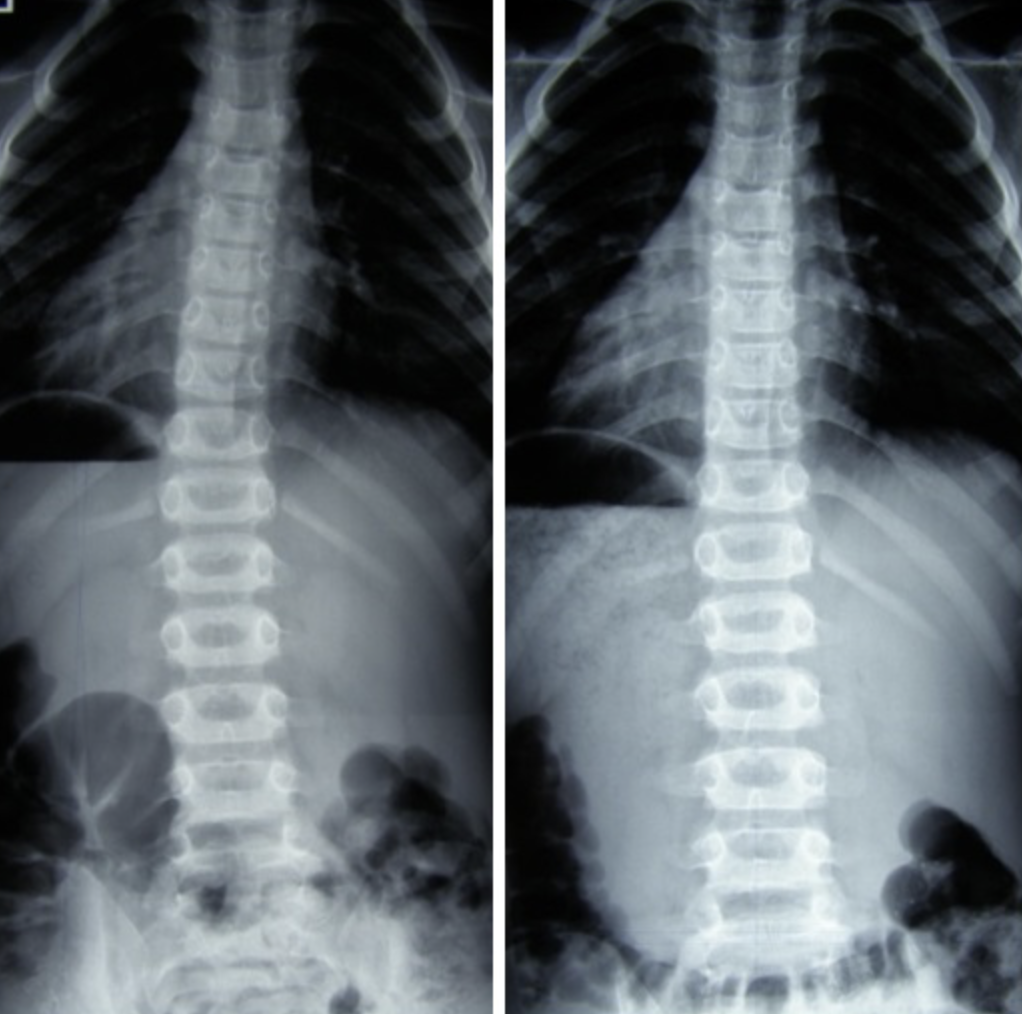

Dawid – 7 lat

Skolioza jednołukowa (statyczna) – zdj. z lewej. Korekcja uzyskana w trakcie jednej wizyty – zdj. z prawej